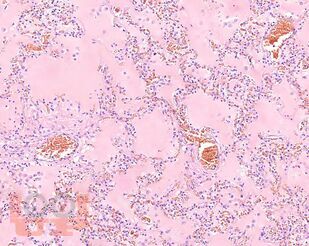

В учебном пособии представлен теоретический материал, перечень макропрепаратов и микропрепаратов, демонстрирующих типовые проявления патологических процессов. В цветных иллюстрациях и в описании микропрепаратов сделан акцент на наиболее важных гистологических изменениях, позволяющих на светооптическом уровне диагностировать и дифференцировать состояния, отклоняющиеся от нормы, в том числе с использованием различных гистологических окрасок. Пособие помогает выделить главные аспекты изучаемых патологических процессов, организовать и конкретизировать учебный процесс.